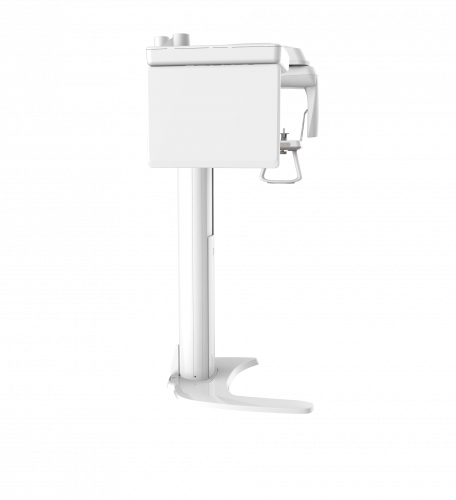

| TYPE | TOP VIEW | FRONT VIEW |

|---|---|---|

|

PaX-i (Pano) |

|

|

|

PaX-i SC (Pano/Scan Ceph) |

|

|